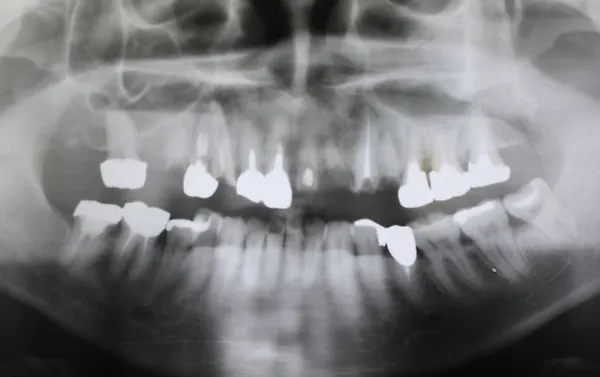

6入れ歯にしないブリッジ治療【ケース1】

H20.6.2のレントゲン

歯槽膿漏の為、上の6本の歯を抜き、上の右端から左端まで繋げたブリッジを作りました。

H31.1.25のレントゲン

H21.2.21に上の歯(ブリッジ)が完成しました。

左の写真は10年ちょっと経過したH31.1.25日に撮影した写真で、経過良好と思われます。

下顎も虫歯と歯槽膿漏のため長く持たせるために左下奥歯の一本を抜歯し残りを繋げて作りました。